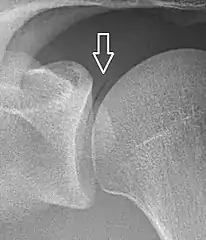

A vacuum sign, or vacuum phenomenon, is a normal finding on shoulder X-rays.

Pneumarthrosis is a common normal finding in shoulders[7] as well as in sternoclavicular joints.[9] It is believed to be a cause of the sounds of joint cracking.[8] It is also a common normal post-operative finding at least after spinal surgery.[10] Pneumarthrosis is extremely rare in conjunction with fluid or pus in a joint, and its presence can therefore practically exclude infection.[8]